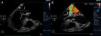

Transesophageal echocardiogram (3-chamber view). (A) Ruptured aneurysm of the anterior mitral valve leaflet. The long arrow points to the entry site and the small arrow points to the exit site of the aneurysm; (B) color Doppler image showing two mitral regurgitation jets: a small jet through the leaflet coaptation point (small arrow) and a much more significant one through the aneurysm (long arrow).

Transthoracic echocardiography (TTE) showed multiple aortic valve vegetations (some prolapsing into the left ventricular outflow tract), mild aortic regurgitation and a large saccular bulge originating from the anterior mitral valve leaflet and protruding into the left atrium with severe mitral regurgitation (Figure 1); left ventricular systolic function was normal. With transesophageal echocardiography (TEE) it became clear that the saccular bulging on the mitral valve was an anterior mitral valve leaflet aneurysm with two rupture sites (Figure 2). Color flow Doppler showed two regurgitant jets: one through the coaptation margin of the mitral valve leaflets and the other across the perforated aneurysm (Figure 3). There was no evidence of either aortic ring abscess formation or extension along the mitral-aortic intervalvular fibrosa.